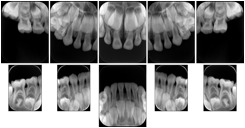

Table OO.1.1-1 shows structured display standard templates, where Viewset ID is based on the Japanese Society for Oral and Maxillofacial Radiology (JSOMR) classification provided by JIRA (Japan Medical Imaging and Radiological Systems Industries Association, www.jira-net.or.jp). Expected or typical teeth to be imaged location, region and designation codes are based on ISO 3950-2010, Dentistry - Designation system for teeth and areas of the oral cavity. For all the hanging protocols listed in OO.1.1-1, the value to use for Hanging Protocol Creator (0072,0008) is "JSOMR" and the value to use for Hanging Protocol Name (0072,0002) does not include "JSOMR" (e.g., "DL-S001A", not "JSOMR DL-S001A").

Table OO.1.1-1. Hanging Protocol Names for Dental Image Layout based on JSOMR classification